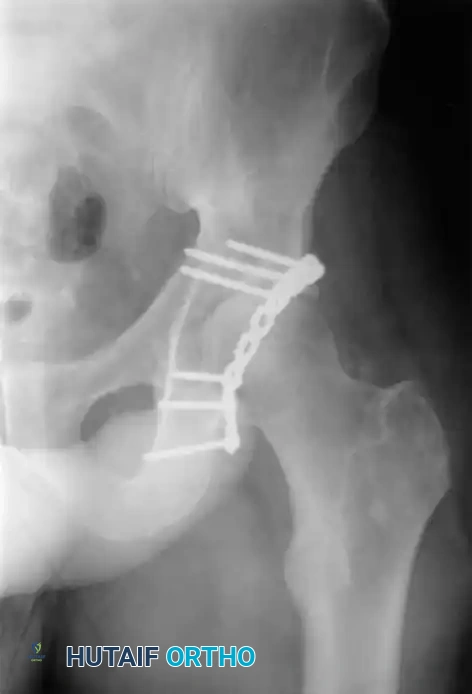

Surgical Approaches

The choice of surgical approach is dictated entirely by the fracture pattern (classified via the Letournel and Judet system) and the location of maximal displacement.

Associated Surgical & Radiographic Imaging

Hutaifortho's Orthopaedic Diagram